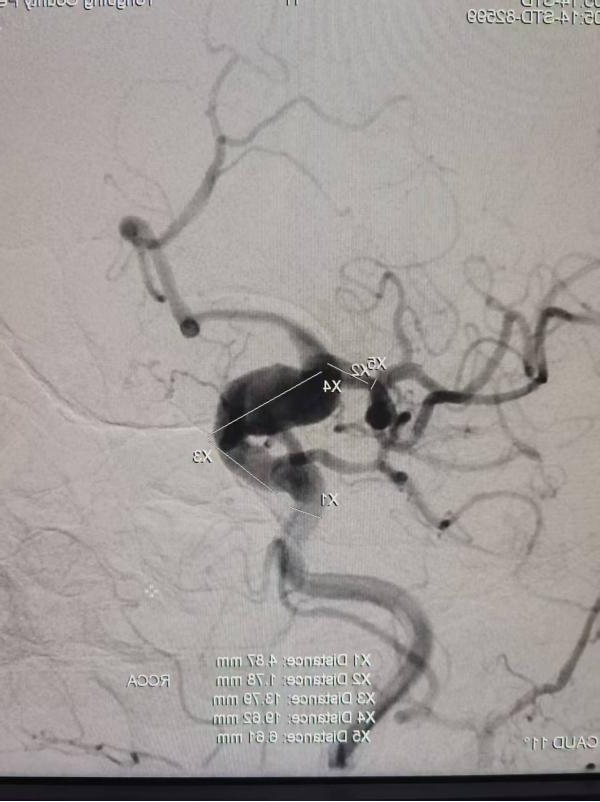

一位因反复头痛就诊的患者,经CT血管成像检查,确诊为颅内巨大动脉瘤,形态不规则,破裂风险极高。面对这一急危重症,孔令超与当地医生共同分析病情,制定诊疗方案。

通过对该病例影像特征的细致观察与风险分层评估,孔令超对巨大动脉瘤的形态学特点、破裂风险因素及介入治疗适应证有了更系统的认识。结合自身技术优势,完成全脑血管造影术,拓展了他在脑血管疾病领域的临床视野,也为科室今后开展动脉瘤介入治疗积累了宝贵经验。